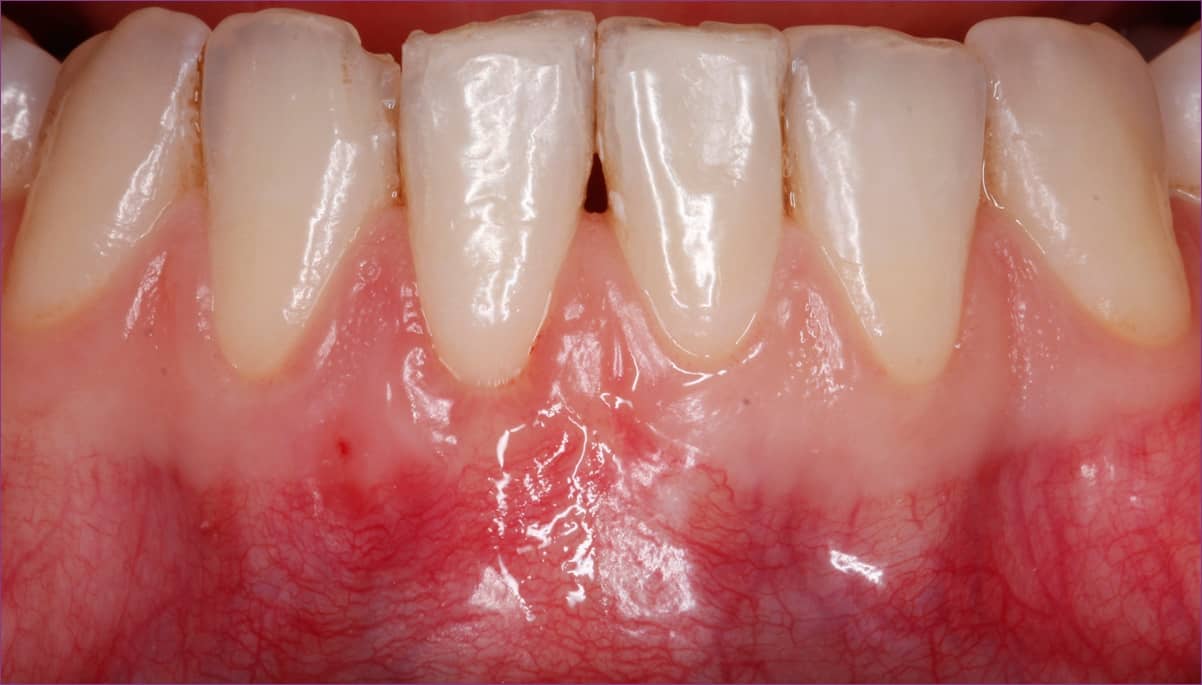

A beavatkozás helyi érzéstelenítésben történt, és nagyjából másfél órát vett igénybe. Az érzéstelenítés után a lehúzódott íny kezelése érdekében az ínyt speciális műszerekkel leválasztottuk és elemeltük a fognyakról, vagyis egy úgynevezett zsebet képeztünk. Ezt követően eltávolítottuk a szájpadlásból a kötőszövetet. A kivett kötőszövet helyére kollagénszivacsot helyeztünk, és a szivacsot varratokkal rögzítettük a zavartalan sebgyógyulás érdekében. A kötőszövetet ezután behelyeztük az ínyvisszahúzódáson átesett fog körüli íny alá, az előzetesen képzett zsebbe, majd varratokkal rögzítettük az ínyt a kívánt pozícióba.

A műtéti beavatkozás után a gyógyulás eseménytelenül zajlott. A varratokat 2 héttel műtét után lehet eltávolítani, ez alatt az idő alatt a pácienst 3 alkalommal hívtuk vissza kontrollra.

A műtét sikerességét az első 2 hét gyógyulási idő nagymértékben befolyásolja, amennyiben ez alatt az idő alatt bármilyen ártalom éri a műtéti területet, az átültetett kötőszövet elhalhat és felszívódhat.